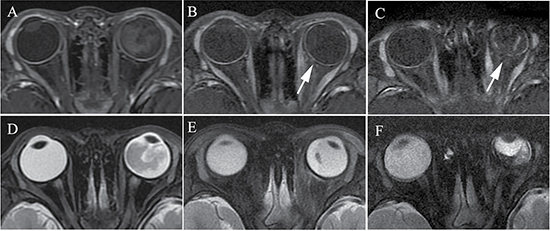

The affected eyeballs after IAC had smaller sized eyeballs than did the eyeballs before IAC (Figure 5) and showed significant differences in the maximum cross-sectional area (MCSA) (t = 2.60; P = 0.004), axial length (AL) (t = 2.35; P = 0.022), and equatorial diameter (ED) (t = 3.90; P < 0.001). In comparison, the sizes of the contralateral eyeballs were slightly larger after treatment than before treatment, with significant differences in MCSA (t = −3.34; P = 0.001), AL (t = −2.46; P = 0.017), and ED (t = −2.75; P = 0.008). There were no significant differences between the affected eyeball and contralateral eyeball before treatment with MCSA (t = −0.142; P = 0.887), AL (t = −0.496; P = 0.622) and ED (t = −0.693; P = 0.491), however, the size of the affected eyeball was obviously smaller than that of the contralateral eyeball after treatment, with a significant difference in MCSA (t = −5.696; P < 0.001), AL (t = −2.958; P = 0.004), and ED (t = −6.761; P < 0.001).

Figure 5: Retinoblastoma diagnosed in a 16-month-old female (patient 4). (A–D) The axial T2-weighted MRI. The right eyeball with retinoblastoma had a size equal to the contralateral eyeball before treatment (A), and became larger in size than the contralateral eyeball in the second month after three cycles of IAC (B). Eyeball atrophy was found in the fifth month after three cycles of IAC (C) and worsened in the tenth month (D).

The other complications observed by MRI before and after IAC are listed in Table 4, and included retinal detachment with subretinal fluid (16.7% versus 56.7%, respectively), subretinal hemorrhage (5% versus 13.3%, respectively), vitreous hemorrhage (1.7% versus 6.7%, respectively), vitreous opacity (3.3% versus 5%, respectively), cataractous lens (0 versus 6.7%, respectively), extraocular muscle inflammation (0 versus 8.3%, respectively), choroidal vascular ischemia (Figure 6) (0 versus 15%, respectively), and vascular proliferation (0 versus 15%, respectively). Secondary enucleation was performed in six eyes at more than 4 months after IAC. The reasons for enucleation in six eyes included vitreous hemorrhage with cataractous lens (n = 1), eyeball atrophy (n = 2) (Figure 5), subretinal hemorrhage (n = 1), subretinal hemorrhage with eyeball atrophy (n = 1), and recurrence with vitreous hemorrhage and cataract (n = 1). There was no patient with metastasis and death.

Figure 6: Retinoblastoma of the left eyeball in a 47-month-old male (patient 5). The axial contrast-enhanced T1-weighted, fat-saturated MRI (A–C) show regular enhancement of the choroid in the left eyeball (A), and decreasing and thinning of the choroid was present when compared with the contralateral eyeball in the first month after two cycles of IAC (B). Intermittent and irregular enhancement of the choroid was present in the fifth month after IAC (C). (D–F) The axial T2-weighted MRI show a progressive shrinkage of the left globe after IAC.